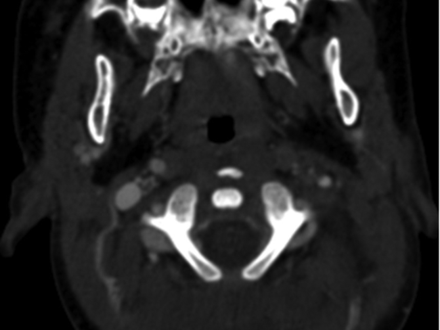

Nine vessels (4 vertebral arteries, 4 ICAs, 1 common carotid artery) in 8 patients ultimately were diagnosed with various grades (I–IV) of BCVI, representing 5.8% (8/137) of the blunt neck trauma population (On-line Table and Figs 2 and 3). The mean age of patients with BCVI was 8.19 ± 6.14 years, ranging from 1.17 to 16 years of age, whereas those without BCVI had a mean age of 9.65± 4.20 years, ranging from 0.67 to 17 years of age. Five patients with vascular injury were not involved in an MVC (On-line Table).

Internal carotid artery injury in patient 6. CTA of the neck demonstrating occlusion of the left internal carotid artery (grade IV injury) at the level of C1 vertebral body in a 1.17-year-old boy who presented neurologically intact after experiencing a witnessed low-speed motor-pedestrian collision.